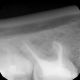

Jak wspomnieliśmy, obrazowa diagnostyka jest niezbędna m.in. podczas wizyty u ortodonty. Lekarza w takim przypadku interesuje rozkład zębów, stan korzeni czy przyzębia. Wszystkie niezbędne informacje do rozpoczęcia leczenia daje właśnie obrazowanie rentgenowskie. Może się okazać, że konieczna będzie jeszcze dokładniejsza diagnostyka – wówczas w naszym gabinecie można wykonać zdjęcie pantograficzne. Ten rodzaj badania uwidoczni np. zawiązki zębów.

Nasze przykładowe realizacje :